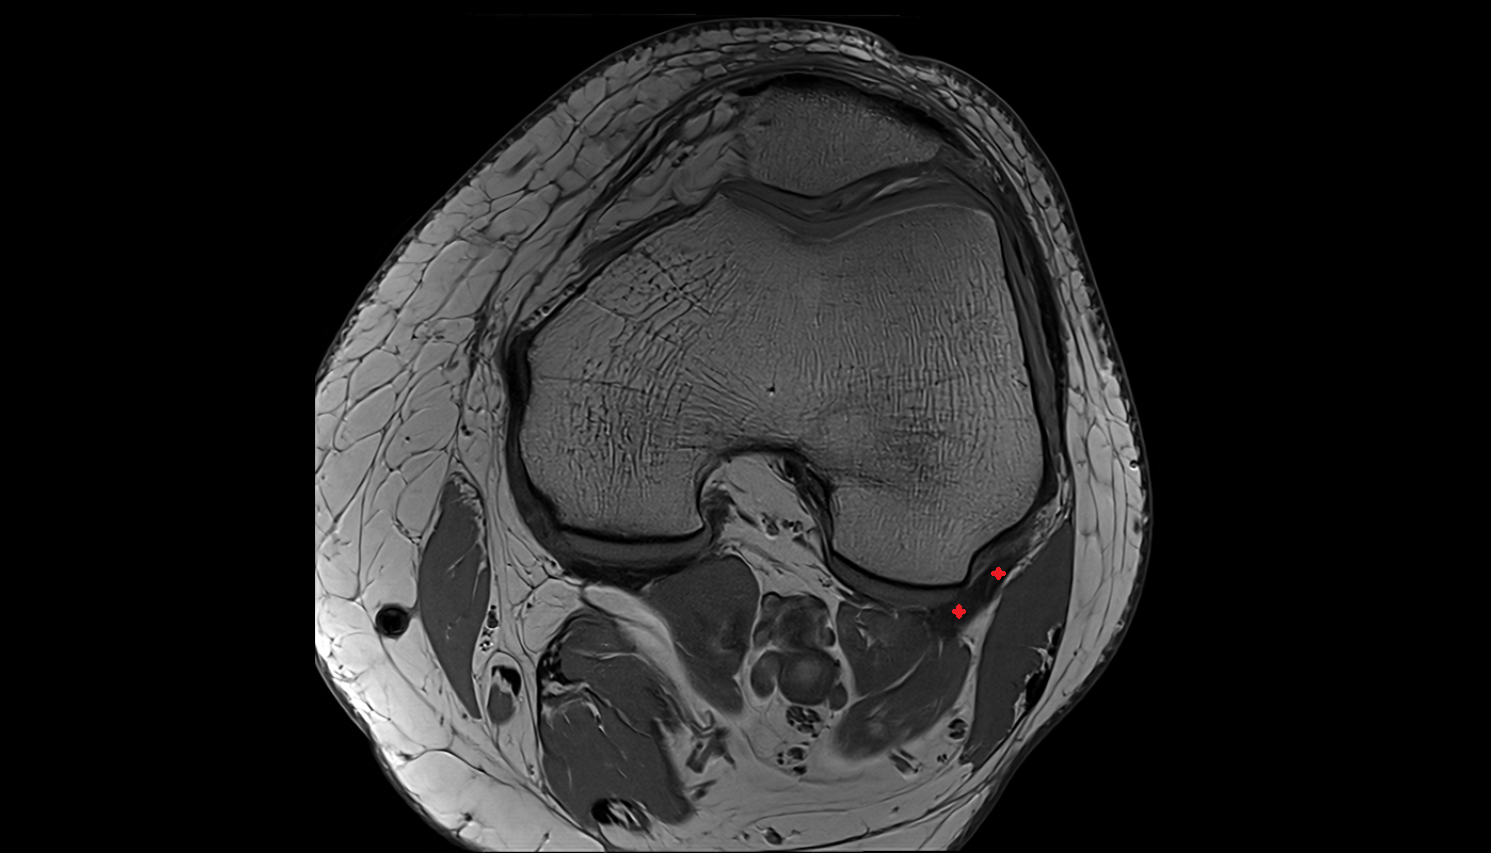

- Patella

- Patellar articular cartilage

- Infrapatellar fat pad

- Suprapatellar fat pad

- Prefemoral fat pad

- Trochlear groove

- Knee Joint